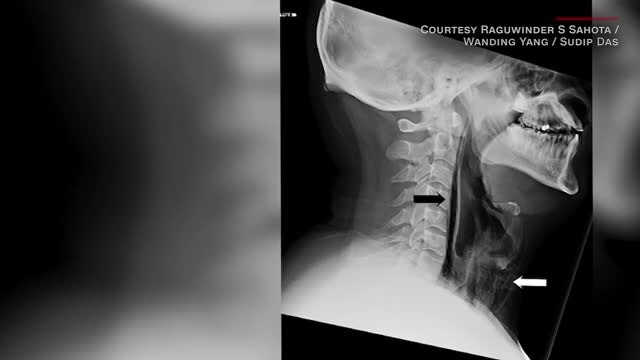

Man hospitalized by suppressed sneeze